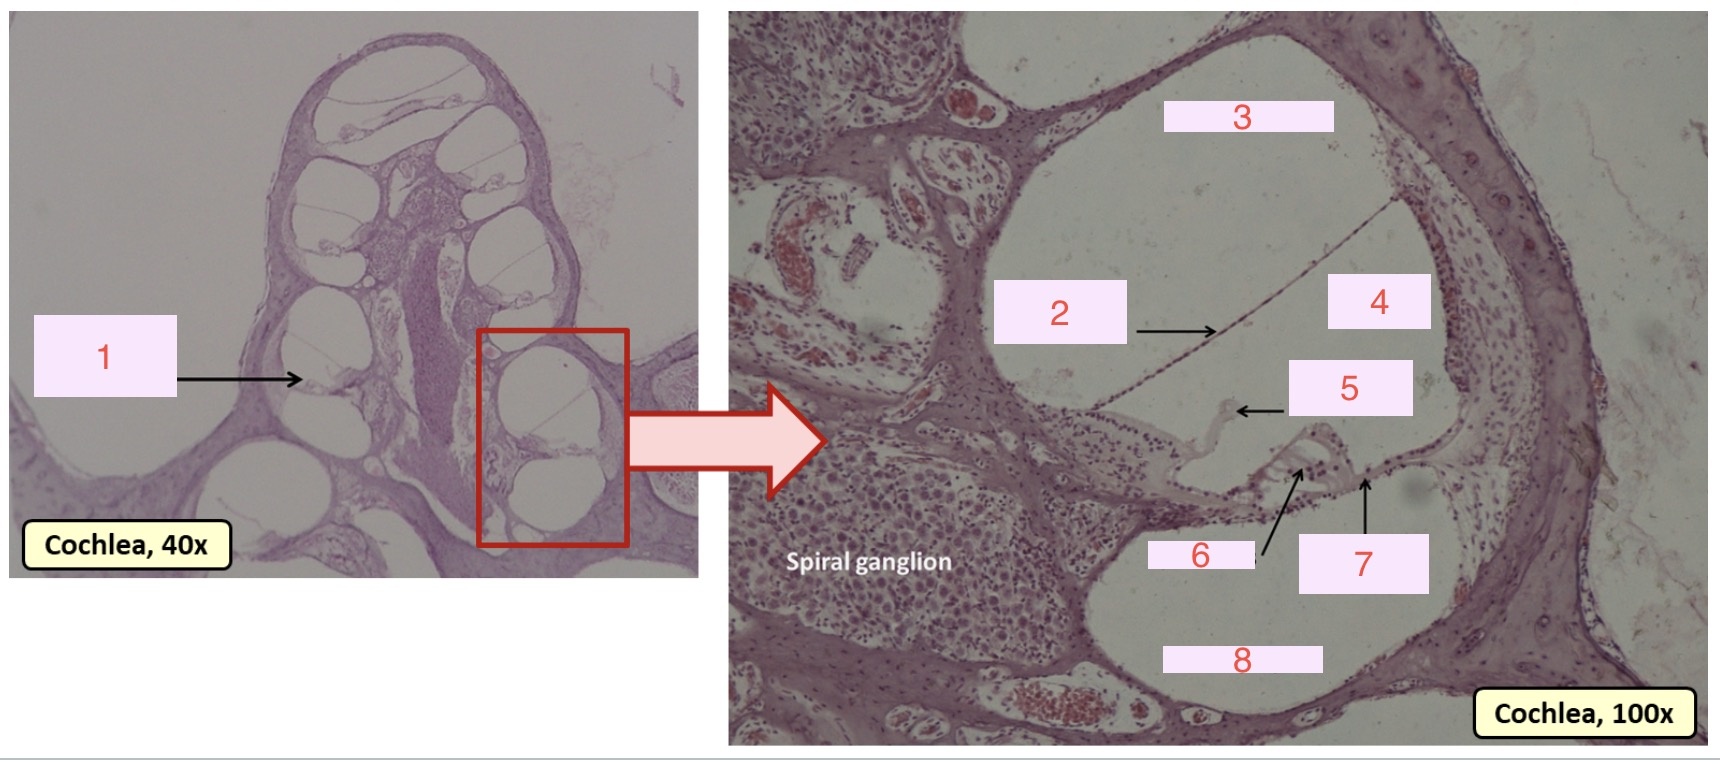

what is 1

organ of corti

what is 2

vestibular membrane

what is 3

scala vestibuli

what is 4

cochlear duct

what is 5

tectorial membrane

what is 6

hair cells

what is 7

basilar membrane

what is 8

scala tympani